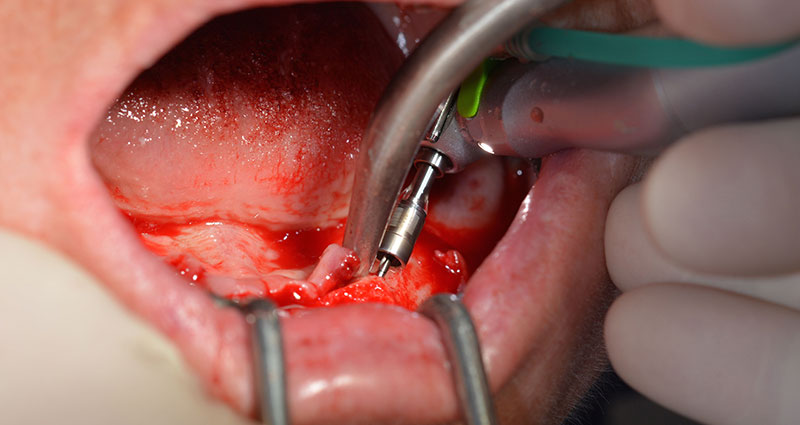

Il prossimo passaggio programmato prevede ancora il posizionamento degli impianti. Solitamente, in questa fase il nostro studio utilizza una coppia di 32 Ncm (Fig. 12 e 13).

contrangolo W&H

Fig. 12

coppia di 32 Ncm

Fig. 13

L'alta solidità è un requisito indispensabile per una ricostruzione immediata. Per garantirla, in questo caso il foro non è stato filettato. L'unità di perforazione Implantmed di W&H è dotata di una modalità speciale per questo scopo, che può essere selezionata direttamente ed è indispensabile in molte situazioni. In fase di posizionamento degli impianti, i giri finali hanno superato il valore di 32 Ncm e sono stati terminati a mano. In questi casi, consigliamo l'utilizzo della funzione autofilettante del sistema di implantologia e la rotazione degli impianti all'indietro e in avanti, per diverse volte. Questo permette all'impianto di assumere gradualmente la posizione finale, evitando un'eccessiva pressione all'osso (Fig. 14).

impianti

Fig. 14